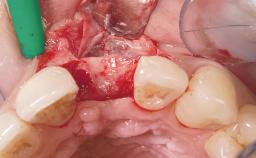

Immediate Placement of an Implant in a Maxillary Left Central Incisor Site

A 33-year-old female patient presented with an upper left central incisor that required extraction after a failed endodontic therapy. The tooth had been traumatized when the patient was a teenager and had undergone several endodontic treatments, including two apicectomy procedures. The patient was in good health and did not smoke. Clinical examination showed that the patient had a high lip line. In full smile, the gingival margins of the upper teeth were visible to the first molars. The gingival margins of central incisors 11 and 21 were only just showing. Examination of tooth 21 confirmed that the tooth was mobile and had hypererupted by 1 mm.

Placement Protocol Immediate implant placement

Tooth Site Maxillary incisor or canine

Socket Morphology Single-root socket

Socket Integrity Damage to one or more bone walls